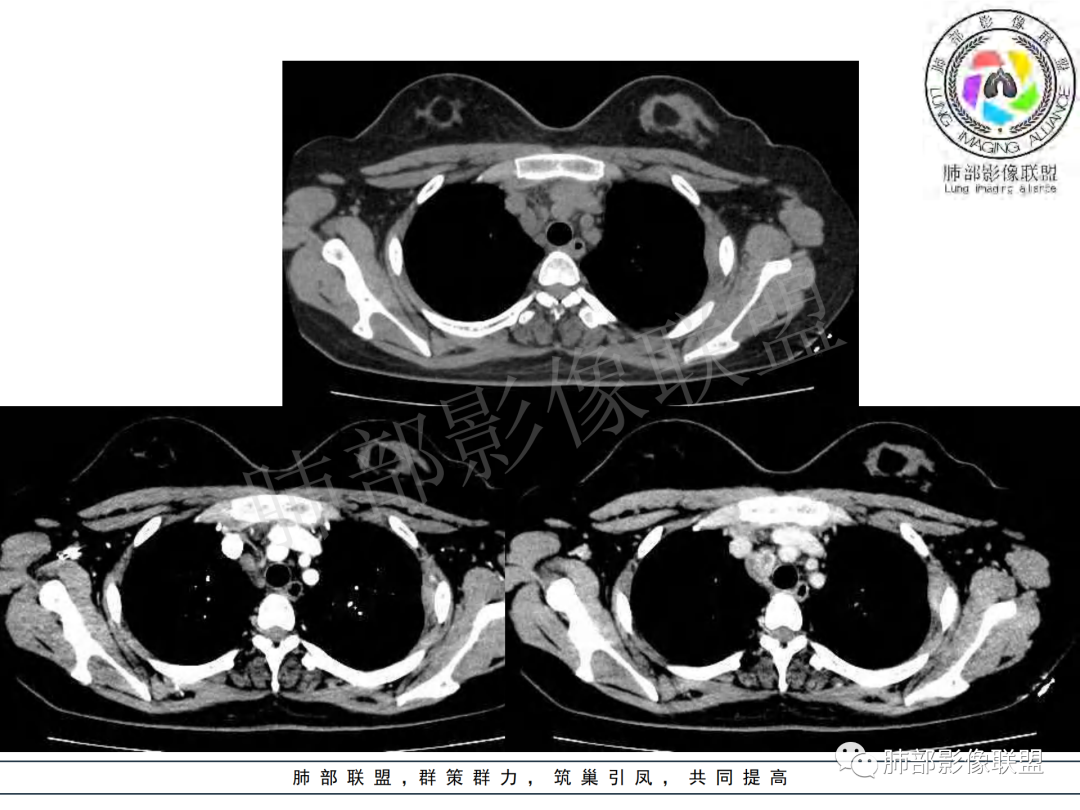

右肺肺门旁肿块,右肺中间段支气管腔内结节,增强强化不均;纵隔多发淋巴结环形强化,右侧少量胸腔积液,临床发热入院,考虑结核,鉴别肿瘤。

右肺门增大,远端花花草草不明显,支气管管壁增厚,纵隔淋巴结环形强化,年龄,病程,考虑炎性病变,结核可能,有个层面支气管截断,有强化,鉴别粘表。

纵隔多组及右侧肺门多发肿大淋巴结,部分融合,不均匀强化,内见斑片状坏死区及环状强化,后者坏死边界尚清晰,肺门区肿大淋巴结与肺组织边界不清,年轻女性,8个月病史,发热首发症状,考虑淋巴结核并向肺内侵及(破溃?),鉴别淋巴瘤

女,20,病程长达8月,发热、胸痛、右侧胸腔积液病史。胸部CT:右肺门旁不规则肿块影,右中间支气管腔内结节,纵隔多发淋巴结肿大;强化不均匀,灶性坏死灶,环形强化;右侧少量胸腔积液并局部肉芽肿样突起。年轻女性,长病程,多部位,考虑慢性炎症,结核?鉴别肿瘤。

青年,右肺门增大,见软组织肿块影,部分支气管腔结节,并管腔狭窄,增强后明显不均匀强化,伴纵隔多发肿大淋巴结,环形强化,考虑恶性,类癌,鉴别支气管内膜结核

右肺门不规则肿块,向气管腔内生长,不均匀强化,其内粘液栓,纵隔淋巴结增大,部分有坏死,胸膜结节强化,考虑恶性,粘表?类癌?鉴别结核

右肺肺门旁肿块,右肺中间段支气管腔内结节,增强强化不均;纵隔多发淋巴结环形强化,右侧少量胸腔积液,考虑结核可能,鉴别肿瘤。

年轻女性,慢性病程,发热、胸痛。右肺门旁不规则肿块影,纵隔多发淋巴结肿大;强化不均匀,环形强化;右侧少量胸腔积液;首先考虑结核,鉴别肿瘤,结节病。

女性,20岁。高热、畏寒。右肺上叶近肺门区不规则肿块,周围斑点、片小结节影伴肿大淋巴结,肿块包绕并突入右主支气管腔内,增强后肿块不均匀强化,淋巴结环形强化中心低密度,考虑结核。

本例患者,年轻女性,慢性病程,多次抗感染治疗效果不佳,实验室检查示白细胞及中性粒细胞不高,不支持普通细菌感染,虽然肺泡灌洗液X-Pert检测阴性,结合患者胸部CT结核感染亦不能排除,胸部CT主要表现为右侧肺门及纵隔淋巴结肿大,仔细观察不难发现右中间支气管内新生物凸向管腔内,增强扫描,右肺门(10R)及纵隔淋巴结(2R,4R)明显不均匀强化,内部呈不规则低密度无强化区,被周边高强化区包绕(环形强化)的特点,首先应当想到纵隔淋巴结结核诊断。淋巴结分布亦不符合肺部恶性肿瘤迁徙途径。